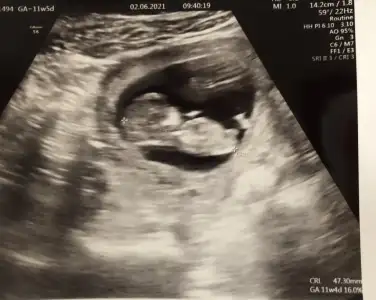

Merhaba fotoğraf 10. Haftadan karın ultrasonu bakar mısınız?